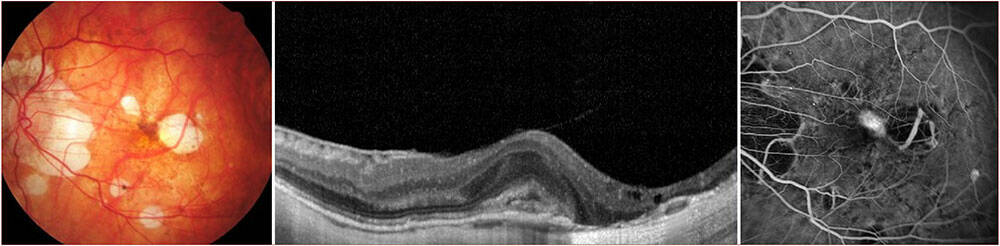

Figure 1. (A) Néovaisseau choroïdien myopique accompagné de fluide sous-rétinien.

(B) OCT B-scan horizontale identifiant du fluide sous-rétinien. Il existe une lésion hyperréflective à bords flous avec une hyporéflectivité postérieure et l’absence d’effraction de l’épithélium pigmentaire. (C) La diffusion tardive à l’angiographie à la fluorescéine confirme le diagnostic.